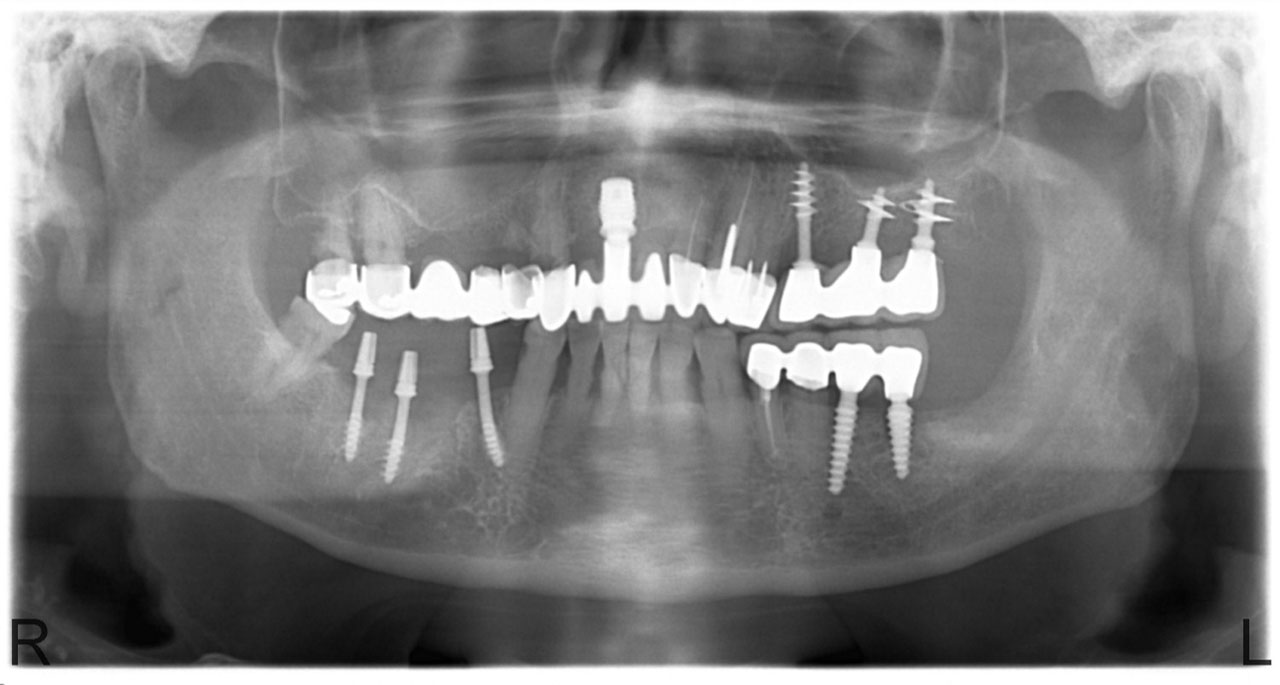

• esettanulmany-07

Teljes fogatlanság.

• esettanulmany-14

Alsó- felső fogatlan állcsont teljes implantációs helyreállítása.

• esettanulmany-08

Műtét másnapján, implantátumok a szájban.